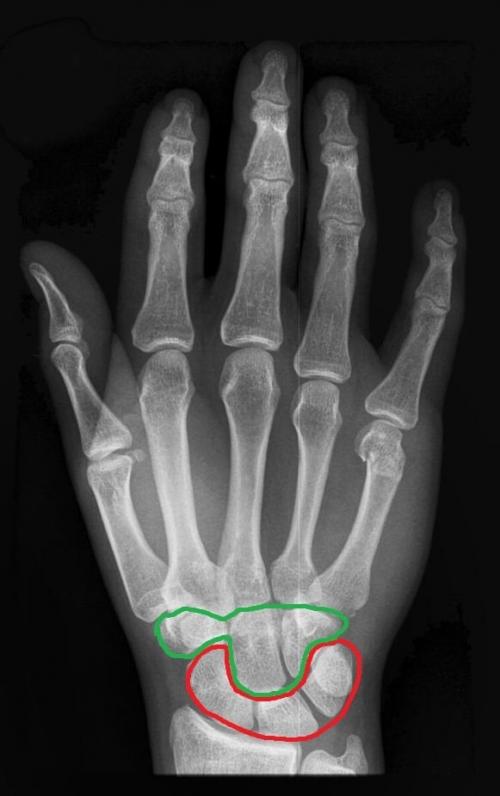

Я решил немного раскрасить этот скучный рентгеновский снимок. Красным цветом я выделил запястье, голубым — пясть, а зелёным — кости пальцев (фаланги).

На этом рисунке я я выделил красным цветом проксимальный ряд костей запястья, а зелёным — дистальный.

А теперь давайте сориентируемся на настоящем рентгеновском снимке и попробуем на нём найти проксимальный и дистальный ряды костей запястья (цвета такие же):